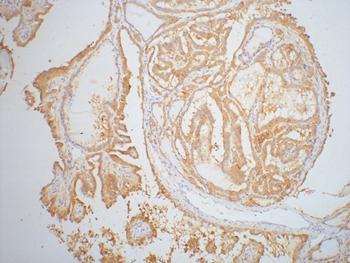

IHC (Immunohiostchemistry)

(Immunohistochemical analysis of paraffin-embedded human-colon using antibody diluted at 1:50.)